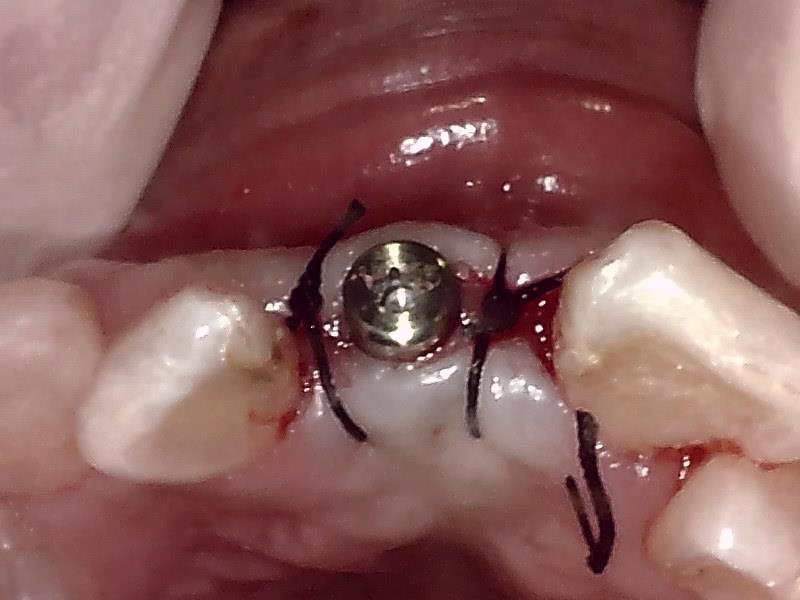

減張切開した歯肉を縫合した状態です。

ヒーリングアバットメント装着して歯肉を縫合する。

抜糸後、2週間経過した歯肉の状態です。